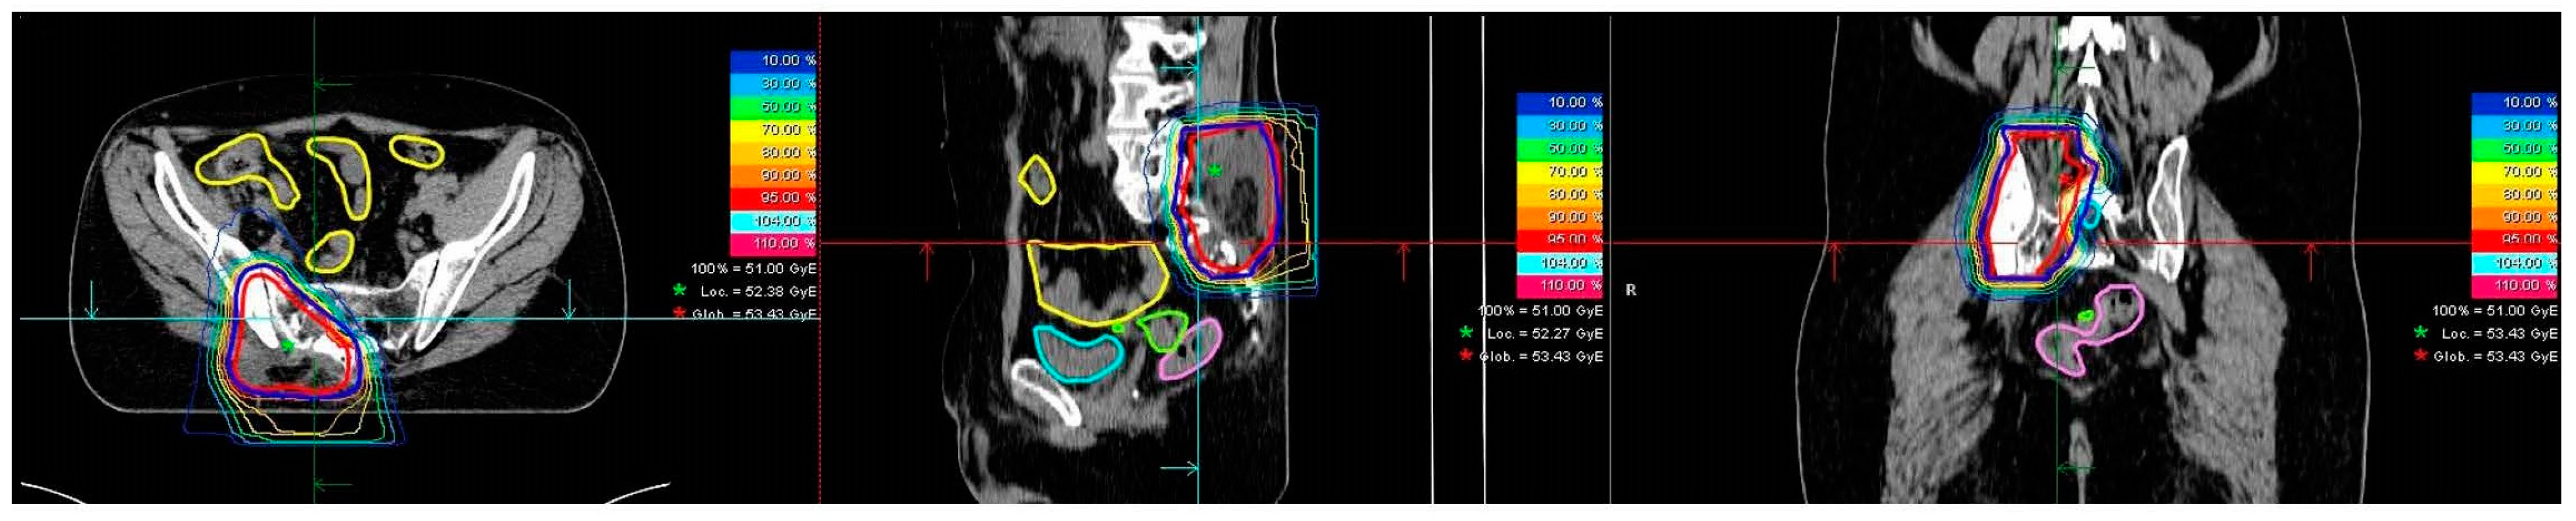

2.2. Radiotherapy

| Type of radiotherapy (n) | ||

| proton | 18 | |

| carbon ion | 3 |

| Recurrent tumor treated in definitive/additive/ adjuvant setting (carbon ions) | n = 3 | |||

| median total prescribed dose (range) in Gy (RBE) | 51 | |||

| median single prescribed dose (range) in Gy (RBE) | 3 | |||